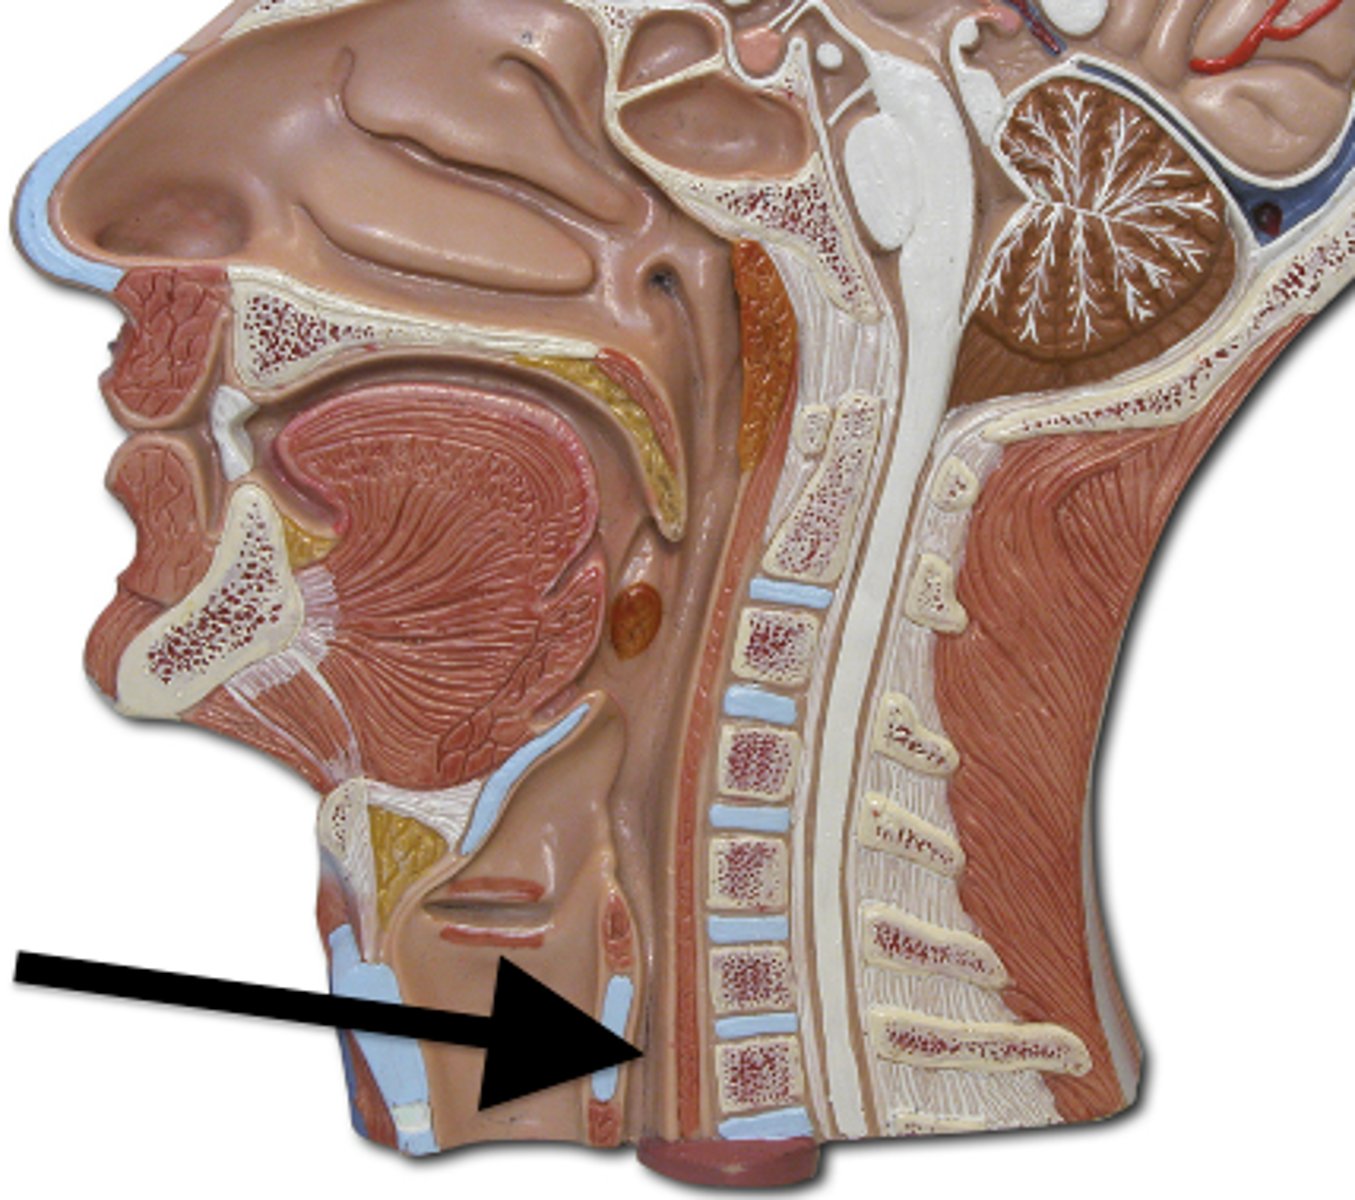

Pharynx

Esophagus

oropharynx

esophagus

Epiglottis

laryngopharynx